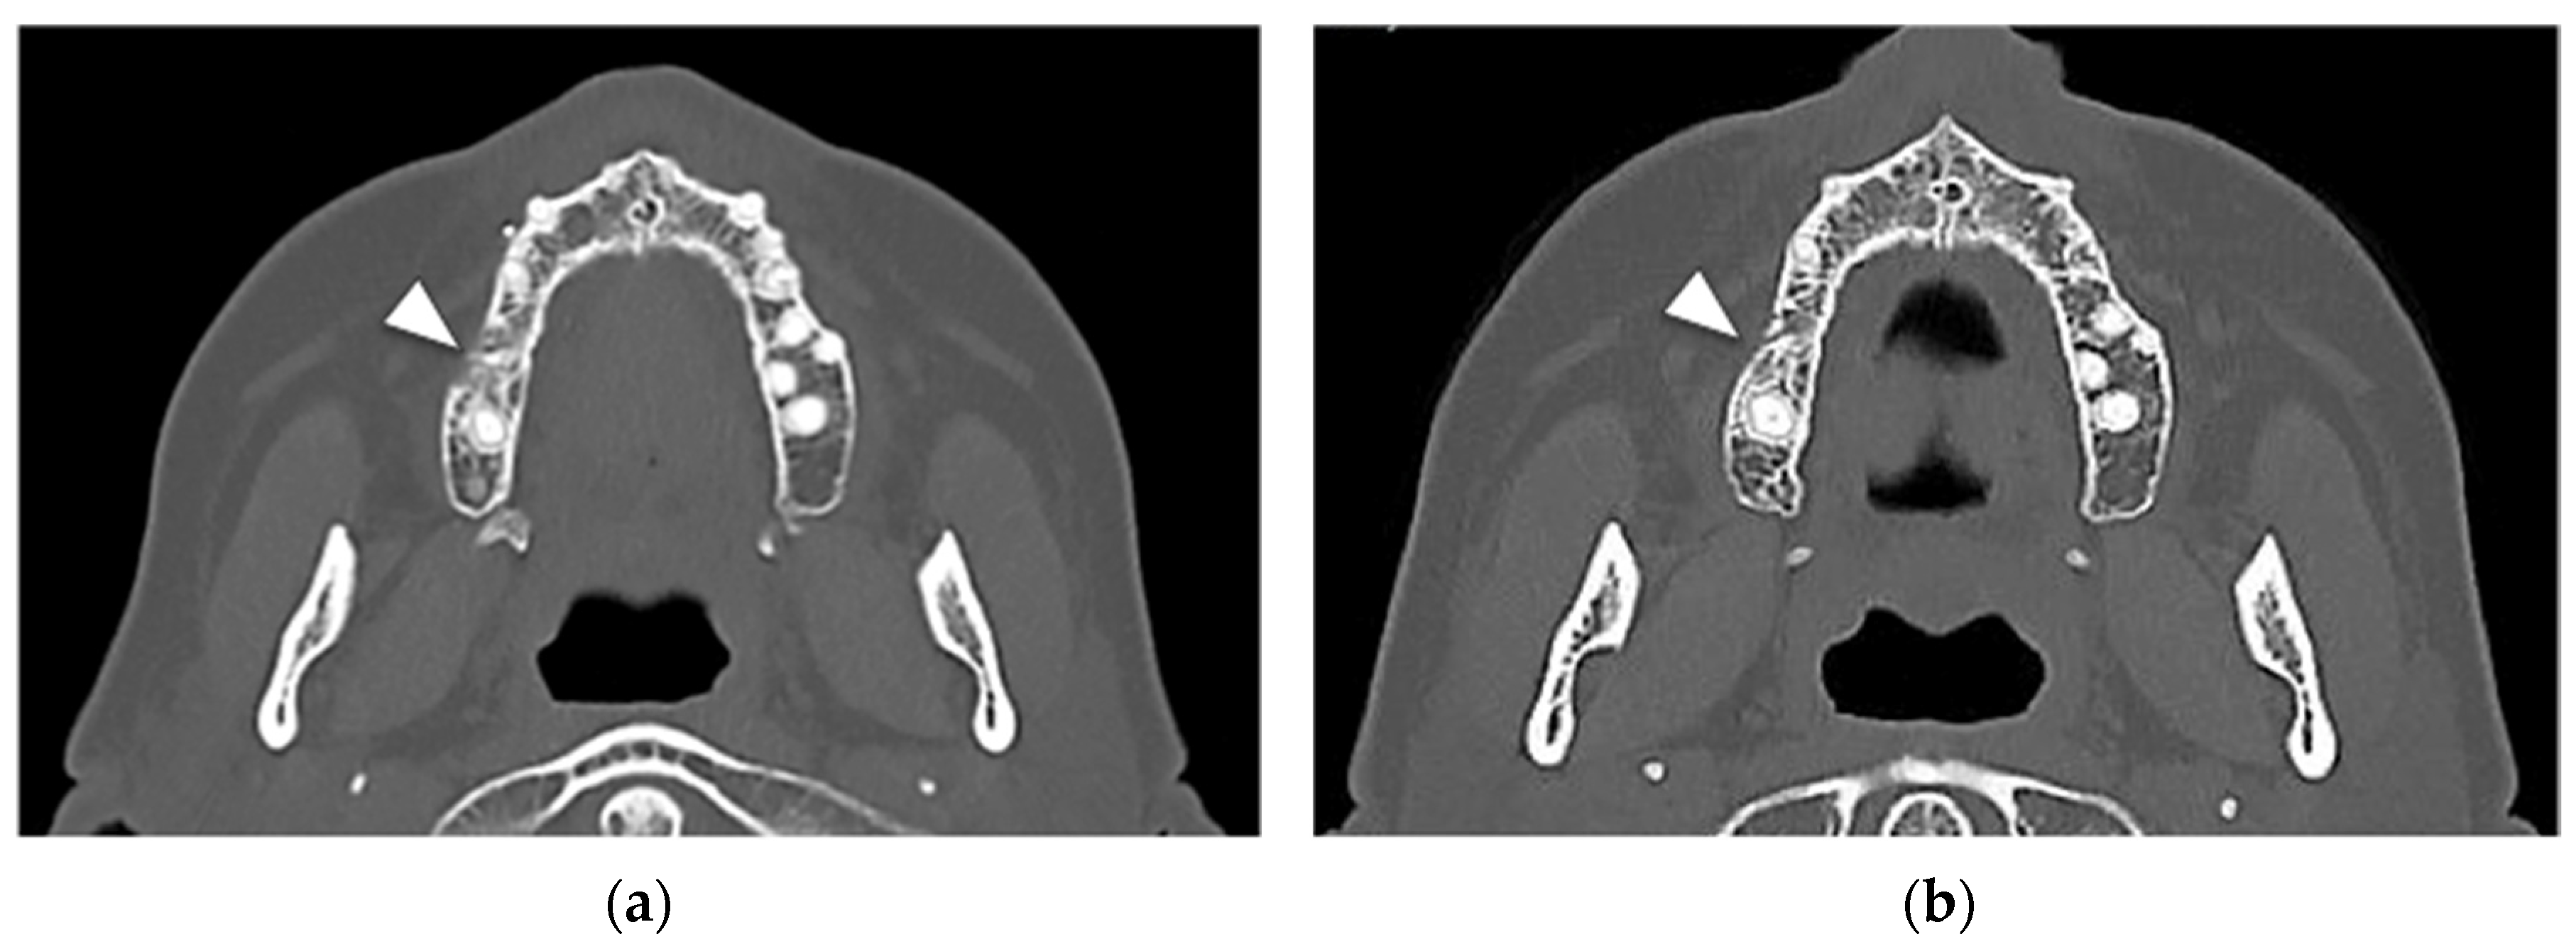

At the 6-month post-operative CT scan, new bone formation was observed in the alveolar socket of the first right upper molar, with a regular trabecular pattern. No signs of bone marrow sclerosis were detected at the right upper molar area (Figure 5a).

At the 1-year CT scan, no bone alterations were present (Figure 5b).

Figure 5. (a) Six-month post-operative CT axial scan with clear aspects of newly formed alveolar bone at the site of surgery (first right upper molar); a residual cortical interruption is maintained in the vestibular aspect without bone focal sclerosis (white arrowhead); (b) Axial CT at one year showing an almost complete continuity of the cortical bone with an alveolar crest width comparable to the contralateral site and resulting from bone repair (white arrowhead); the posterior region of the upper right jaw showed a regular bone architecture and trophism.